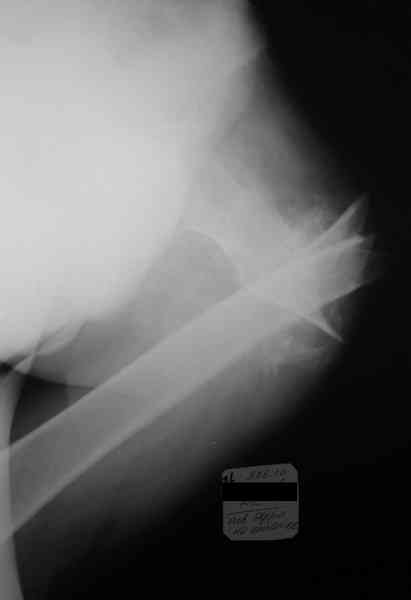

Re: Неправильно консолидирующийся перелом бедра

Рентгенограммы приложить не получается